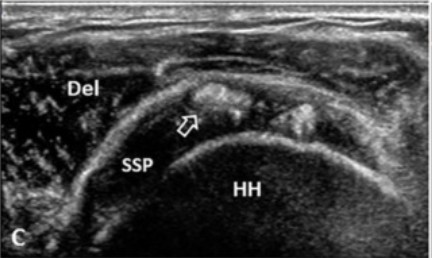

En la exploración estándar del supraespinoso, con el paciente en posición de Crass modificada y la sonda en eje longitudinal, el tendón sano muestra un patrón fibrilar organizado, hiperecoico y homogéneo.

La cortical del troquíter, que usarás como referencia inferior, aparece como una línea blanca brillante y continua. Por encima del tendón, el deltoides. Entre ambos, la bursa subacromial, prácticamente invisible cuando está sana.

Cuando aparece una calcificación, rompe ese patrón de una forma que no deja demasiadas dudas. Pero cómo lo rompe depende mucho de en qué fase se encuentra el depósito.